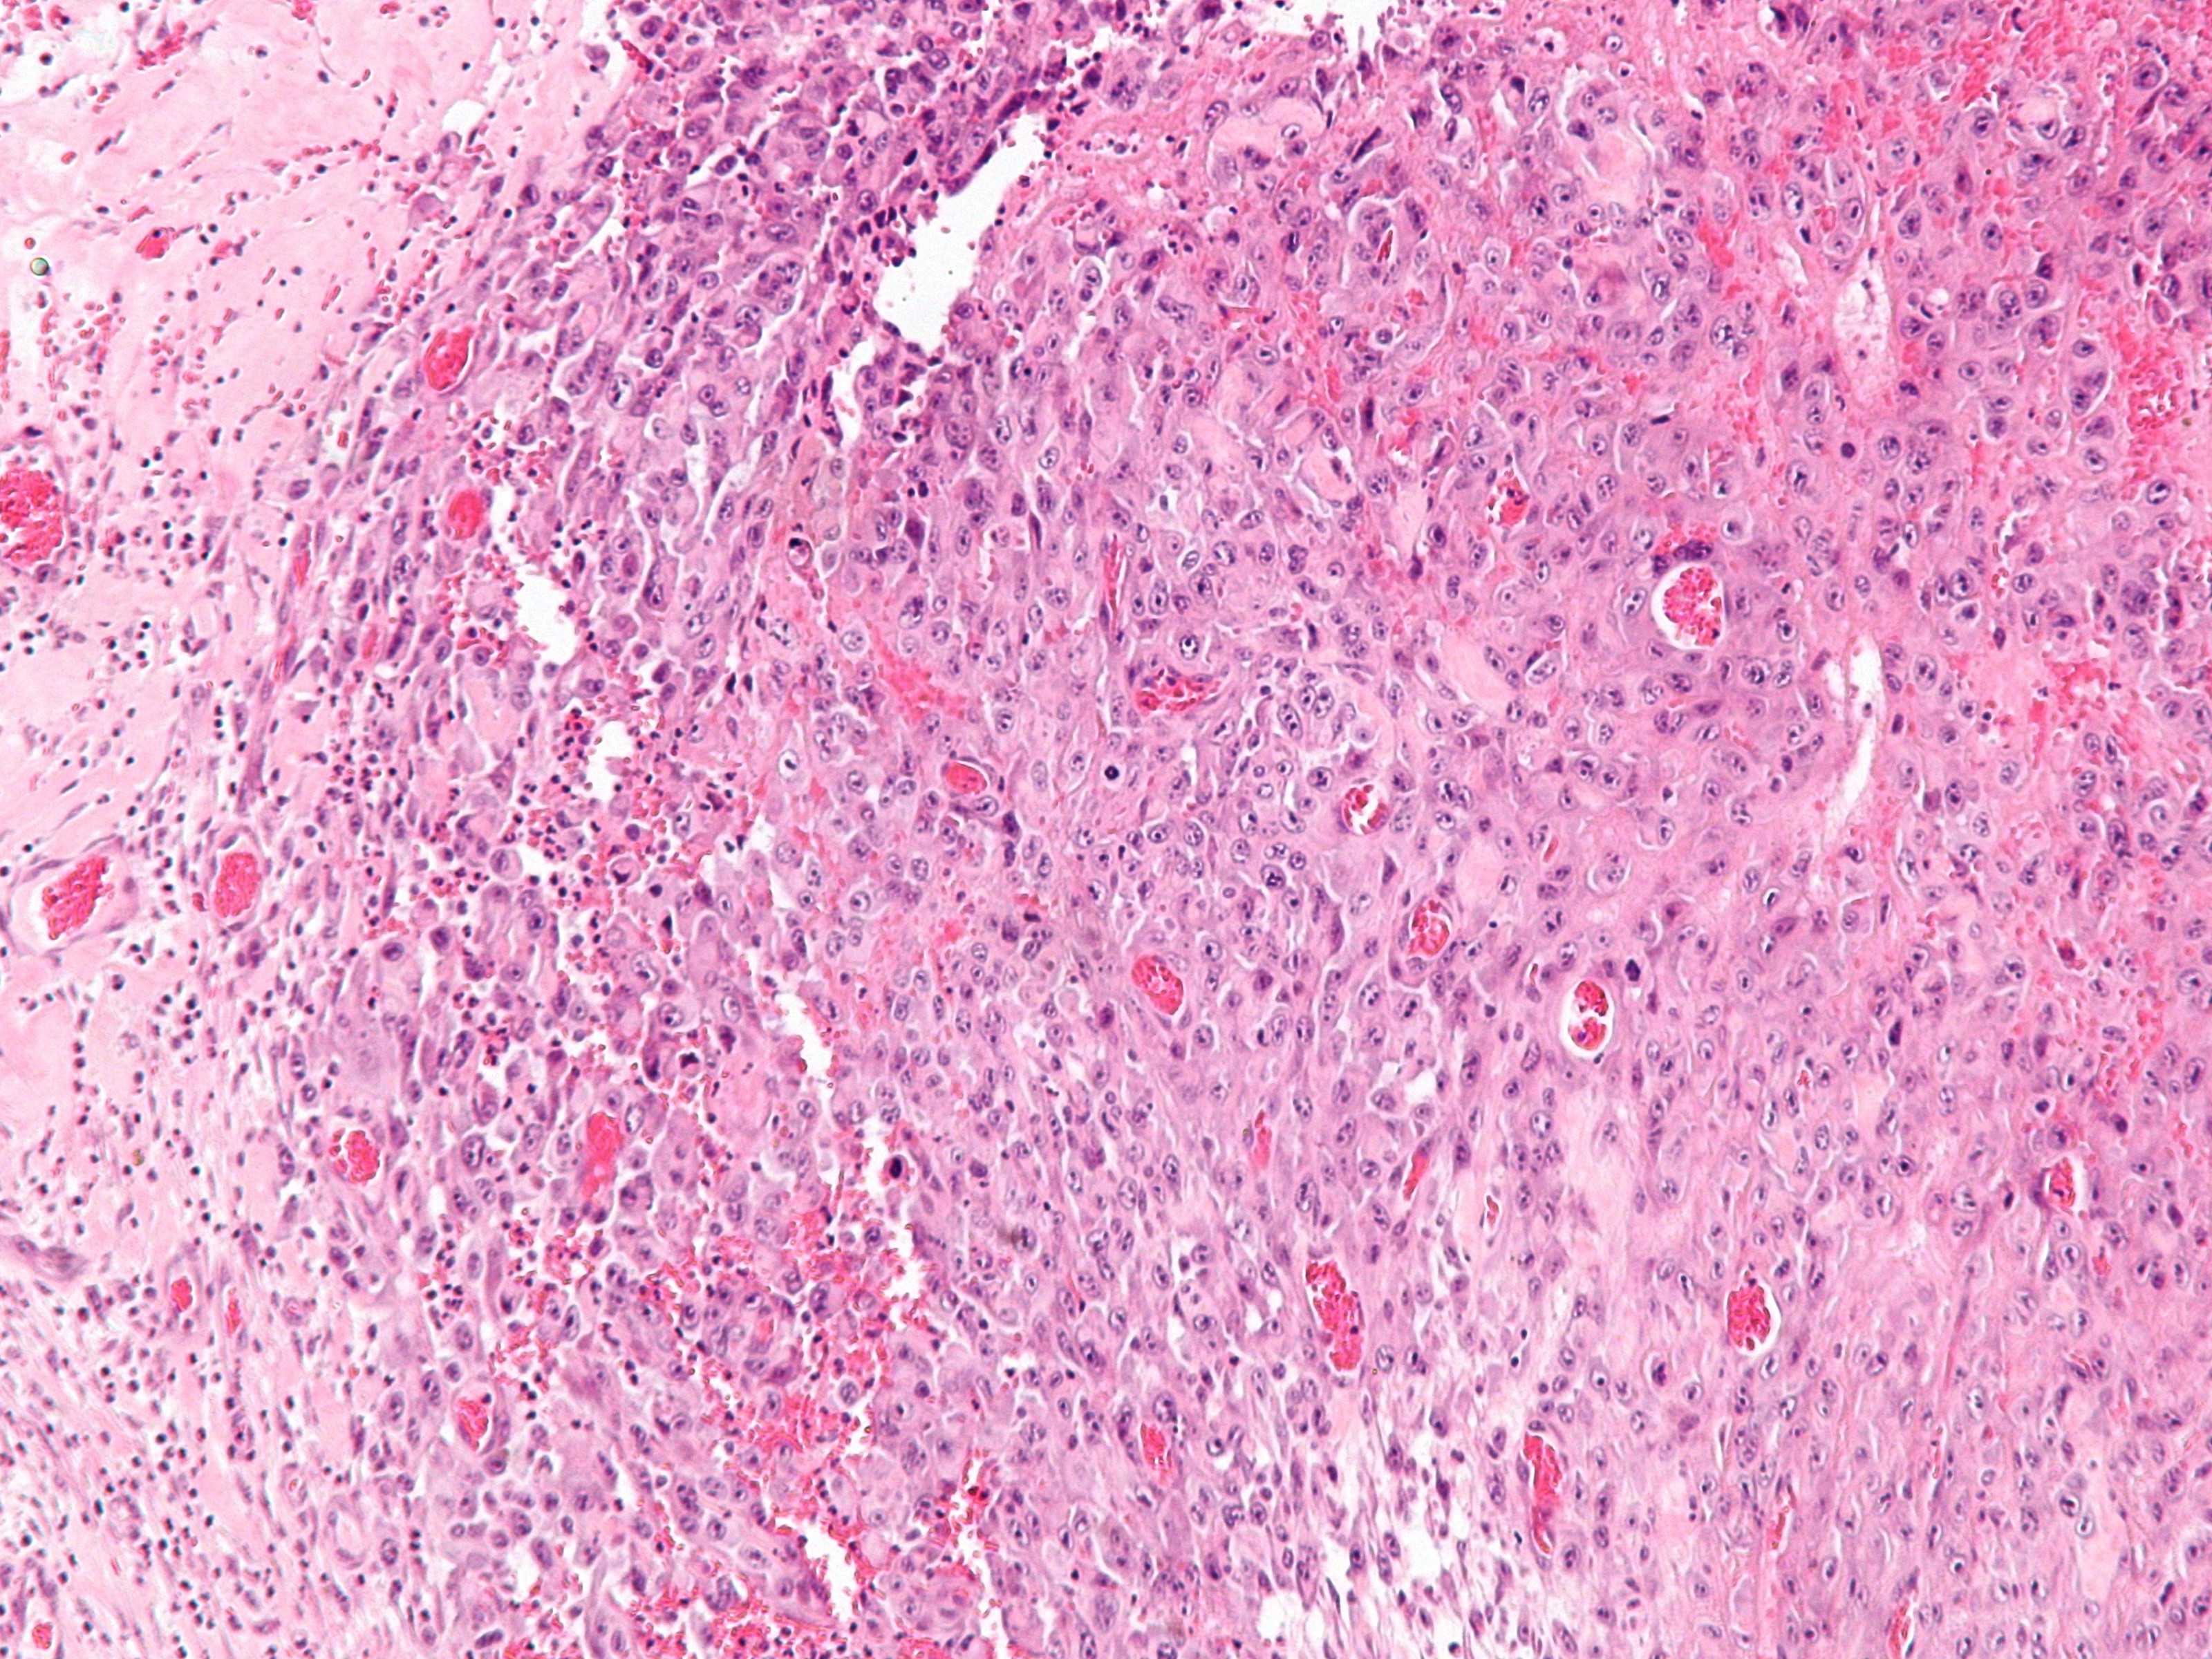

![Epitheloid sarcoma (click on photo to enlarge) [source: Michael Bonert (Nephron) - Wikimedia - Creative Commons License 3.0] Epitheloid sarcoma](../../../images/epithelioid-sarcoma-2z.jpg) |

![Epitheloid sarcoma (click on photo to enlarge) [source: Michael Bonert (Nephron) - Wikimedia - Creative Commons License 3.0] Epitheloid sarcoma](../../../images/epithelioid-sarcoma-3z.jpg) |

| epitheloid sarcoma |

epitheloid sarcoma |

PA-Foto's: Michael Bonert (Nephron) - Wikimedia (Creative Commons License

3.0).

PA:Nodi opgebouwd uit bleke polygonale cellen met een eosinofiel cytoplasma, in de periferie vaak meer spoelcellig. Centraal in de nodi kan necrose ontstaan. De cellen zijn positief voor vimentine, cytokeratinen, EMA (epithelial membrane antigen), CD34 en CA125, en meestal negatief voor S100, desmine, en FLI-1.